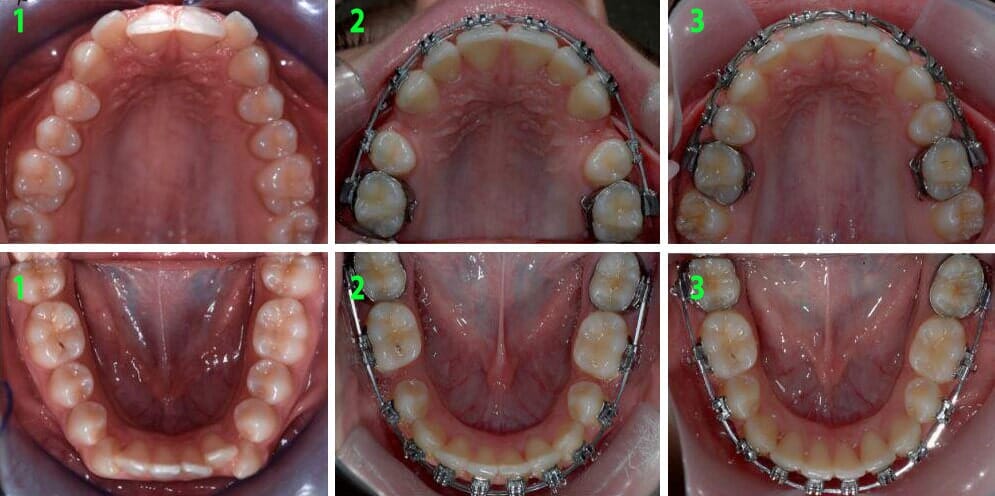

טיפול אורתודונטי שגרתי

כאמור, רוב טיפולי יישור השיניים מתחילים בגילאי 12 – 13 כאשר השיניים סיימו את התחלפותן או נמצאות לקראת סיום ההחלפה שלהן. טיפול כזה מבוצע לרוב באמצעות מכשור קבוע ("קוביות", "גשר") המודבק לשיניים למשך זמן הטיפול. טיפול כזה כולל בד"כ מספר שלבים שיכולים להתבצע בו- זמנית או בסדר שונה מהמתואר להלן:

• הרחבת הקשת העליונה, במידה וישנו צורך כזה. לרוב תבוצע באמצעות מכשירים אשר מותקנים באזור החך.

• הדבקת סמכים (לרוב מתכתיים) על השיניים. לאחר הדבקת הסמכים מבוצעות הפעלות של המכשיר הקבוע ("מתיחות"), במטרה לבצע את הפעולות הבאות:

1. סידור קשתות השיניים- במידה והבעיה העיקרית של המתרפא היא שיניים עקומות, הרי שעיקר השיפור יושג כבר בשלב הזה.

סידור קשתות השיניים